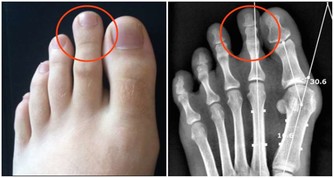

為什麼痘痘反覆難去除?(男女有別,避免誤區!) 男女長逗的區別

區別一:皮膚更油膩,男性肌膚的油脂分泌量比女性大,所以更容易堵塞毛孔,誘發炎症 區別二:男性毛髮多毛孔更粗大,細菌感染機會高,所以長青春痘的機會更大 區別三:女性肌膚細膩,毛髮長,長痘的機率小,程度更輕 區別四:男性長痘年齡普遍晚於女性,但是長痘的程度嚴重過女性 區別五:女性由於生理期內分泌的變化影響 ,更容易反覆長痘 6大祛痘誤區應避免 你是否有這樣的祛痘經歷呢?總是忍不住用手去擠痘痘,結果痘痘越來越嚴重?試了很多祛痘產品,結果痘痘消了又長?看了很多祛痘帖,自己DIY面膜祛痘,結果沒有成效甚至適得其反?...痘痘反反覆復難以去除,小心是陷入了祛痘誤區哦!